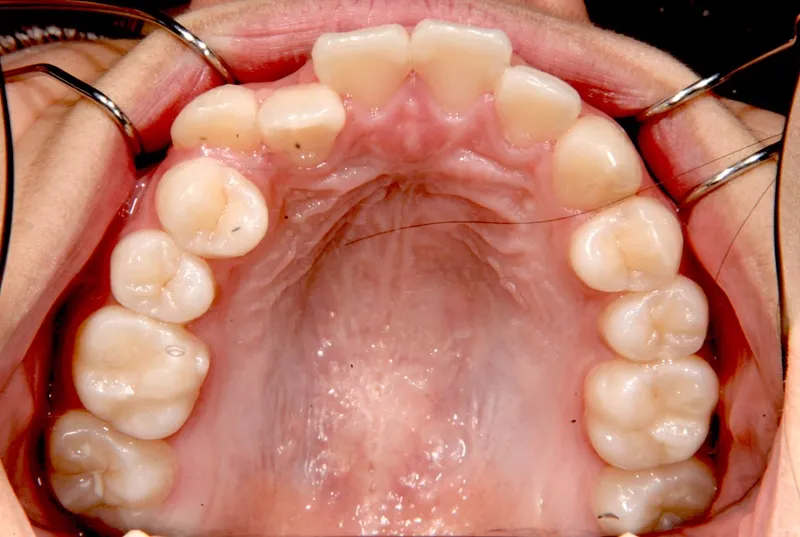

初診時年齢 中学生 (女性) 主訴 八重歯・噛めない

診断名 叢生・開咬 装置名

状態 ガタガタ・でこぼこに生えている(叢生)

八重歯(叢生)

歯ががたがたで、噛み合わせもずれています。